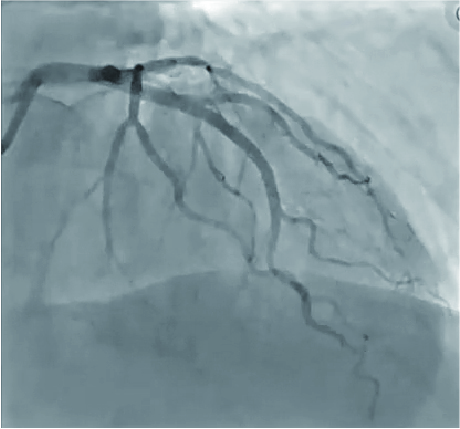

Coronary angiography

TruePhysio® pressure microcatheter was advanced to the distal D1 without any effort and given an FFR value of 0.90 (Fig. 5), with satisfactory angiographic results (Fig. 6)